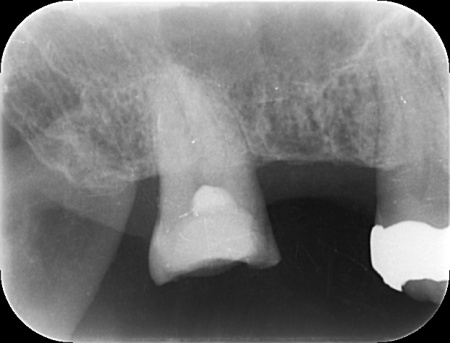

| カウンセリング | 拝見したところ、右上の奥歯には複数の歯をつないだ被せ物であるブリッジが入っていましたが、被せ物の内部で虫歯が再発していました。 レントゲンを撮影して詳しく調べた結果、虫歯は比較的大きく歯の神経に近い深さまで進行していることが確認できました。 このまま放置すると、神経に炎症が起こって強い痛みが出る、神経が死んでしまい歯を温存できなくなるといった可能性があります。 以上のことから、ブリッジを取り外して虫歯を治療する必要があると診断しました。 |

①MTA歯髄温存療法(神経を残す治療) ②根管治療(神経を取る治療) 患者様は「歯を長持ちさせたい」との希望から、①MTA歯髄温存療法を選択されました。 まずブリッジを慎重に取り外し、虫歯を確認します。 数週間後、しみたり痛んだりする症状は認められず、コールドテストとバイタルテストでも歯の神経が問題なく機能している状態であると判断できました。 神経が温存できていることを確認できたため精密な型取りを行い、虫歯の再発リスクが低く強度も高いセラミックのジルコニアでブリッジを新たに作製しました。 |